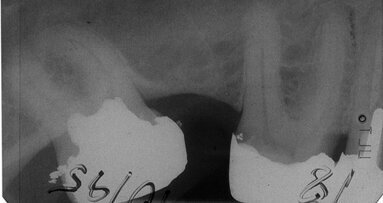

GEILENKIRCHEN – Die Vitalamputation (VitA) von Milchzähnen ist eine allgemein akzeptierte Maßnahme zum Erhalt ihrer ...